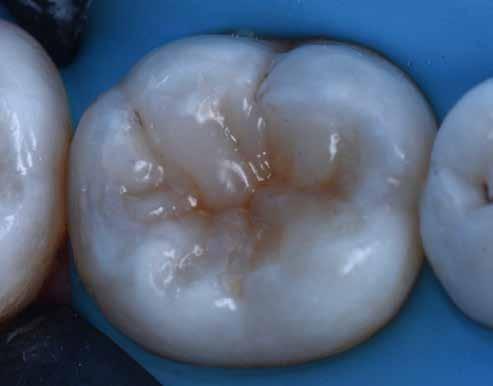

A korábban rutinszerűen használt amalgámtömések mára a legtöbb páciens számára esztétikailag nem elfogadhatóak, hanem fogszínű, természethű restaurációt várnak el. Kaméleon effektussal bíró kompozitokat használva, akár szakavatott szem számára is láthatatlan módon, funkcionálisan és esztétikailag is helyreállítható a fog. Az adhezív technika fejlődésének és az alacsony zsugorodási stresszel bíró kompozitoknak köszönhetően a kiterjedtebb II. osztályú üregek direkt módon is felépíthetőek. Megfelelő protokollokat követve lépésről lépésre kiszámíthatóan elérhető a kívánt végeredmény.

Az 53 éves hölgy páciens jobb felső 6-os fogában látható amalgámtömés cseréje volt a cél. A tömés mellett secunder caries és az amalgám következtében létrejött mesialis zárólécen áthaladó repedés, továbbá mesialis caries figyelhető meg (1. ábra). El kellett kerülni, hogy a tömés kifúrásakor az amalgámtörmelék a páciens szájába kerüljön, esetleg ebből valamennyit lenyeljen, a kezelés első lépésként kofferdám izoláció került fel a jobb felső kvadránsba (2. ábra). A kapocs a 1.7 fogra került, ezzel kényelmesen helyet teremtett a későbbiekben felkerülő matricarendszernek. Az egyszerre több fog izolálása lehetővé teszi, hogy a szomszédos fogak referenciául szolgáljanak a restauráció felépítése közben.

A régi amalgámtömés eltávolítását követően caries indikátor segítette a carieses laesio megfelelő kitisztítását a pulpa expozíciója nélkül. Ezután kerülhetett sor az ideális üregdesign kialakítására, továbbá a zománcszélek finírozására (3. ábra) Az approximális box megnyitása során az alátámasztatlan zománcprizmák eltávolításra kerültek, ezzel is csökkentve a secunder caries képződés veszélyét. Az így kialakuló forma elősegíti a matrica megfelelő adaptációját, végül pedig az approximális box határainak a hozzáférhetőségét, így finírozás során ez jobban kontrollálható és polírozható.

A Palodent V3 matricarendszer felhelyezését követően a zománc 10 másodperces szelektív savazása, majd lemosása és leszárítása után történt a kavítás bondozása Prime & Bond Universallal.

Kulcslépés: a II. osztályú üreget a matricarendszer segítségével I. osztályúvá lehetett átalakítani.

A pontosabb széli záródás érdekében célszerű a matrica illesztési határába némi folyékony kompozitot felvinni (NeoSpectra ST flow A2), majd megvilágítás nélkül a zárólécet paszta kompozittal (NeoSpectra STHV A2) felépíteni, miközben a kifolyó fölösleges folyékony kompozit eltávolításra kerülhet. Így ki lehetett használni és kombinálni a két különböző konzisztencia előnyeit.

A polimerizációt követően kerülhet sor a matricafeszítő gyűrű, valamint a matrica eltávolítására. A Palodent V3 fülekkel ellátott matrica kialakításának és a speciális PinTweezers csipesznek hála, a feszes kontaktpont ellenére a matrica könnyedén eltávolítható. Az éket viszont a kezelés végéig

célszerű bennhagyni, elkerülve egy esetleges nemkívánatos vérzést (4. ábra)

A matrica és gyűrű nélkül az approximális fal magassága, valamint a szomszédos fogakhoz viszonyítható dimenziók jobban megállapíthatóak. A jobb térlátás és a nagyobb mozgástér precízebb eredményhez vezet, csökkentve ezzel az utólagos finírozás mértékét, továbbá a részletgazdagon kialakított anatómiai struktúrák torzulásának az esélyét. Az üreg mélyebb részei SDR Plus A3-mal kerültek feltöltésre, majd NeoSpectra STLV A3-mal kiegészítve vált teljessé a dentin pótlása (5. ábra), ezzel létre lehetett hozni egy homorú formájú kromatikusabb alapot.

Ezt követően csücsökről csücsökre haladva a felső hatosokra jellemző anatómiai struktúrák, megfelelő orientációval bíró csücsöklejtők és elsődleges barázdák Neo Spectra

HV A2 anyagból kerültek kialakításra (6. ábra). Apró „kompozit-hurkákkal” kiegészítve létrehozható a csücskökön belüli tagoltság, ezzel kialakítva a másodlagos barázdarendszert és egy sokkal kidolgozottabb anatómiai struktúrát (7. ábra). A fogorvos esetleges „művészi hajlamát” is figyelembe véve, a természethű megjelenés barázdafestéssel (Micerium - Stain Brown 2) még tökéletesebb lehet (8. ábra). Ezzel a korábban részletgazdagon kialakított ba-